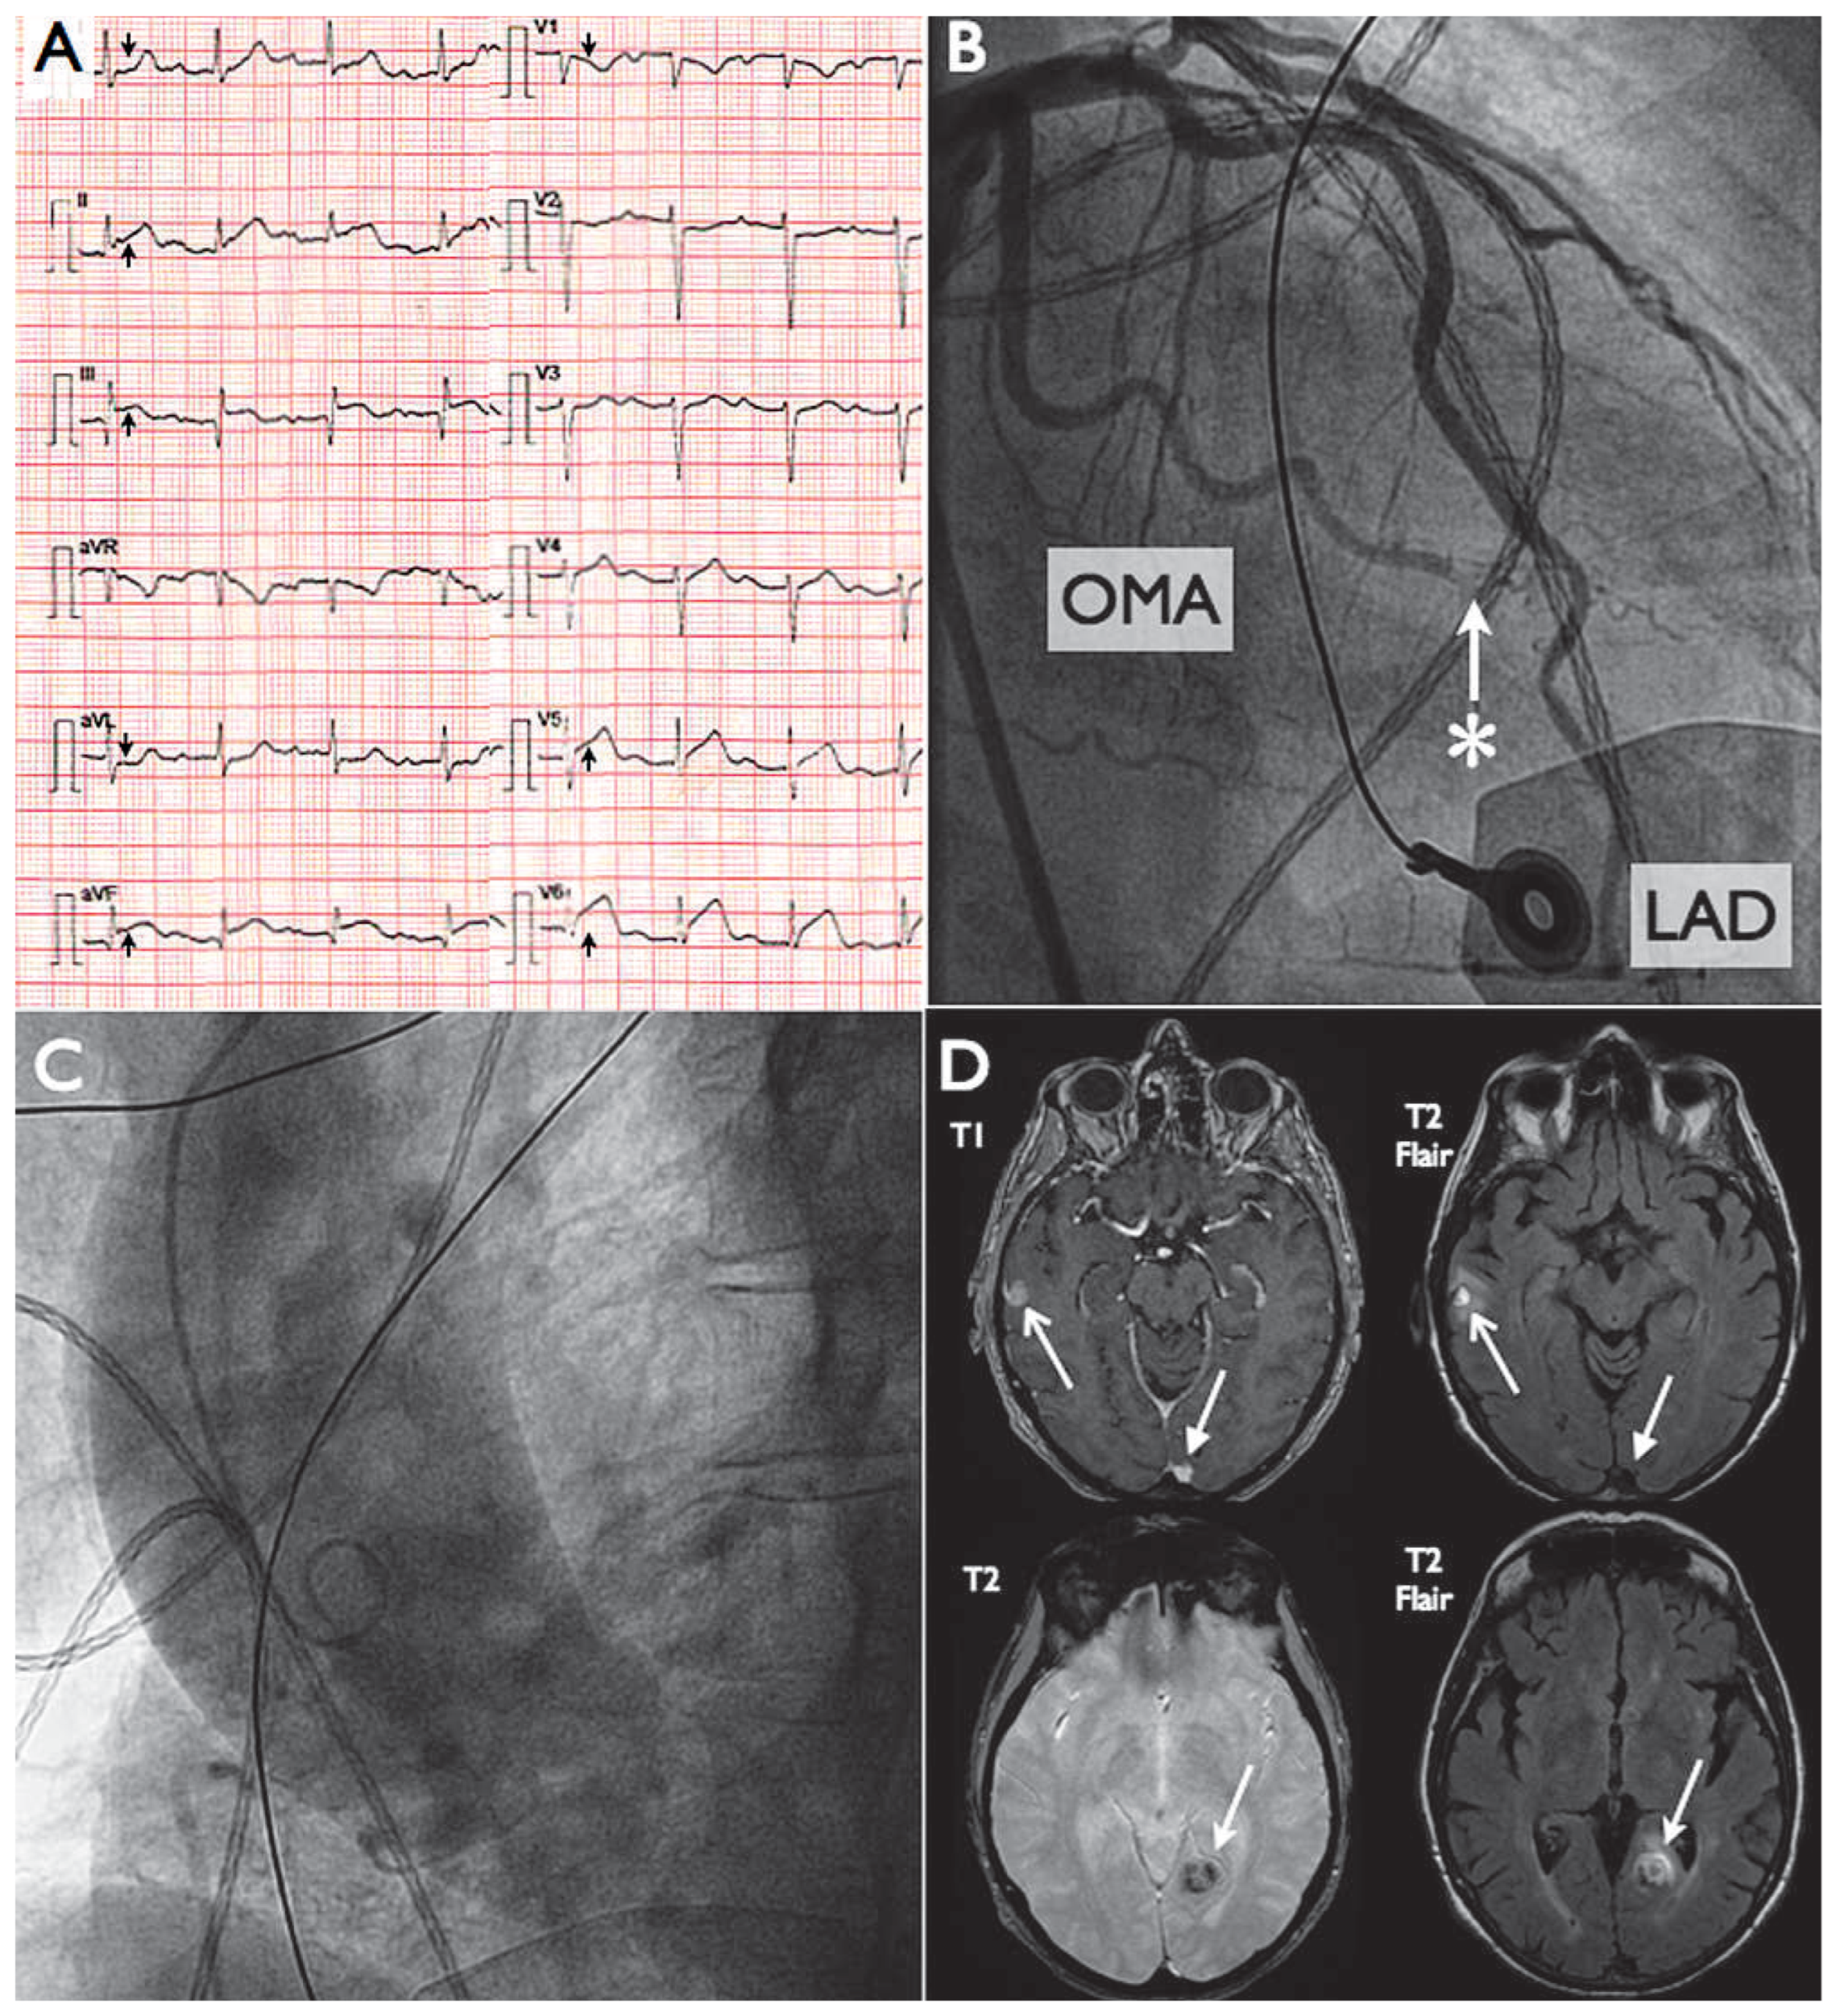

On arrival, the 12-lead electrocardiogram (ECG) showed normal sinus rhythm, first-degree atrioventricular block and a 2 mm ST-elevation in leads II, III avF, V5 and V6 (Figure 1A). Therapy was initiated with aspirin 500 mg, heparin 5000 U and clopidogrel 600 mg. An urgent coronary angiography revealed the distal occlusion of a marginal branch of the circumflex artery but otherwise normal coronary arteries (Figure 1B). The aortogram showed significant ascending aorta dilatation (Figure 1C) as well as severe aortic valve regurgitation. The left ventricular ejection fraction was deemed normal with inferolateral hypokinesia. Considering the history and presentation, a septic embolus was thought to be the cause of the occlusion and, due to vessel tortuosity, distal lesion and spontaneous symptom alleviation no intravascular treatment was attempted. Peak troponin Ic was 12.3 ug/L and total CK 545 U/L. Four different peripheral blood cultures grew penicillin sensitive Streptococcus salivarius (minimum inhibitory concentration <0.125 mg/L). A trans-oesophageal echocardiogram demonstrated a calcified and moderately remodelled bicuspid aortic valve with no evidence of vegetation or abscess and a normal mitral valve. All other findings were in line with the angiographic assessment. The abdominal scan showed a superior splenic infarction and the brain MRI was consistent with multiple, bilateral, embolic lesions with secondary haemorrhage (Figure 1D). The retina, skin and other organs were free from embolic complications. The patient was treated with i.v. ceftriaxone 2 g daily for 4 weeks, all subsequent blood cultures were negative and she remained symptom-free. The severe aortic regurgitation warranted a close cardiological follow-up and to date, the patient has had no further complaints.

Figure 1.

Panel A: ECG demonstrating normal sinus rhythm, first degree atrioventricular block and ST-segment elevation in II, III, avF, V5-V6. Panel B: Coronary angiogram demonstrating an acute occlusion (*) of a distal obtuse marginal artery (OMA) but otherwise normal coronaries. LAD = left anterior descending. Panel C: Aortogram showing dilatation of the ascending aorta due to bicuspid aortic valve. Panel D: Brain MRI – T2 flair and T1 sequences demonstrating a left posterior temporal and right lateral temporal lesion compatible with embolus and hemorrhagic transformation.